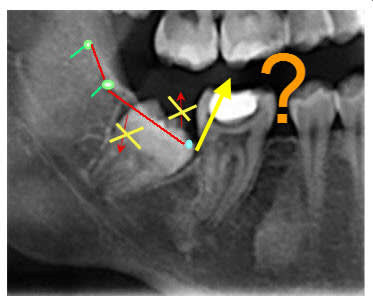

Un orthodontiste me refère une patiente avec le même problème au niveau des dernières molaires (patientes 12 ans) aux ma=xillaires inférieures; il me demande d'exposer les dents. Comment le faite-vous? en profitez-vous pour faire un peu d'ostéoplastie en distal? Dans mon cas l'arcade de 6 à 6 est en place.La distalisation des 6 a empêché l'éruption des 7.

Probl me d axe.. - Eugenol

Redresseur d axe tiwjog - Eugenol